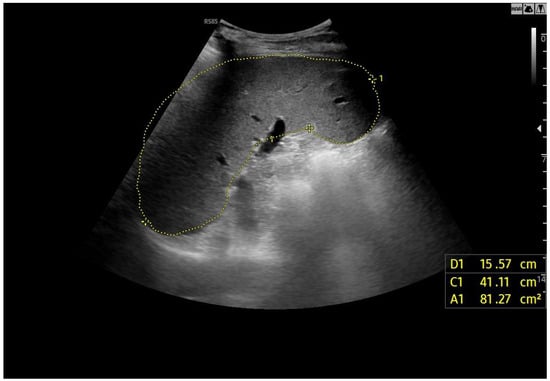

Ultrasound imaging is capable of identifying heterogeneous echotexture and hepatomegaly, which are early indicators of congestive hepatopathy [46]. Several studies have shown correlations between the extent of sonographic abnormalities and the severity of hepatic fibrosis or cirrhosis [36,47,48]. The most common ultrasound findings encompass a nodular hepatic surface, right-lobe volume reduction, smooth-to-rounded contour changes, and irregular outer profiles [49,50,51] (Figure 2). The echotexture appears granular and markedly heterogeneous, with hyperechogenic nodules of varying sizes [49,50,51] (Figure 3, Figure 4, Figure 5, Figure 6, Figure 7 and Figure 8).

Figure 2.

Detail with convex probe in oblique subcostal scan: note the rounded margins, the heterogeneous echotexture, particularly in the left segments, and a marked hypotrophy of the right lobe.